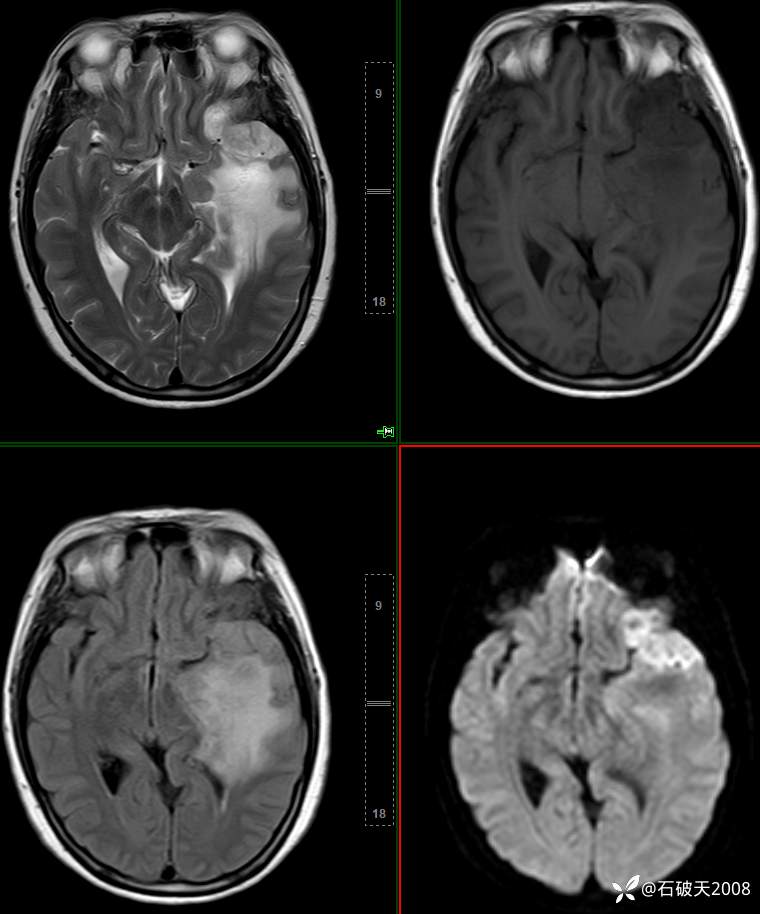

平扫